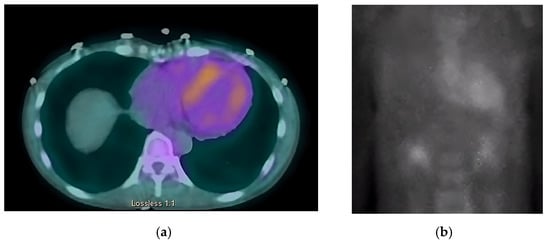

The chest radiograph did not show any acute findings. Electrocardiogram (ECG) (Figure 1) showed normal sinus rhythm with first-degree atrioventricular block, left axis deviation, and low voltage in limb leads. No prior echocardiogram (ECHO) was available, so an initial ECHO was obtained showing preserved ventricular ejection fraction (EF), moderate left ventricular hypertrophy (LVH), stage II diastolic dysfunction, and small pericardial effusion (Figure 2 and Figure 3).

Her overall condition and response to treatment were closely monitored in our clinic with monthly follow-up visits. The patient initially tolerated medications as stated above. However, despite medical management, her overall condition has been deteriorating. She continued to have a poor appetite and lost a significant amount of weight which further contributed to her weakness and fatigue. She has been hospitalized a multitude of times throughout the last two years with ongoing dysphagia, hypotension, orthostasis, syncope, nausea, and vomiting, ultimately being admitted for dehydration and malnutrition. The patient eventually underwent further evaluation by her gastroenterologist, and a percutaneous endoscopic gastrostomy tube was placed for nutrition purposes. She continues to follow up with cardiology and gastroenterology clinics. She was also hospitalized on several occasions with obstructive urinary tract infections and urinary retention, which ultimately resulted in the placement of a chronic foley catheter. She is now being closely monitored by urology services as well. The patient had several repeat ECHOs without major changes from imaging obtained on the initial clinic presentation. The most recent ECHO is without any significant changes. Her EF continues to be normal, and she continues to have moderate LVH and stage II diastolic dysfunction with persistent, small pericardial effusion. Fortunately, she was never hospitalized with symptoms of heart failure. Her current medication regimen includes pantoprazole, amitriptyline, gabapentin, fludrocortisone, midodrine, droxidopa, and metoclopramide. Her main complaints remain to be orthostatic hypotension, syncope, dizziness, weakness, and peripheral neuropathy with resultant insomnia.

On ECHO, the characteristic finding is symmetric biventricular wall thickening (LV > 12 mm, and often ≥15 mm) with non-dilated ventricles and diastolic dysfunction. Biatrial enlargement commonly occurs from elevated ventricular filling pressure and direct atrial amyloid deposition. There is a risk for atrial thrombus formation (in the absence of arrhythmias) as amyloid infiltration contributes to an irregular endocardial surface, decreased atrial contractility, and decreased stroke volume (SV) [33].

Valvular thickening may be present and can help differentiate CA from hypertensive heart disease [27]. EF is initially preserved with systolic dysfunction absent until advanced stages are reached when sequelae of myocyte necrosis and fibrosis start affecting systolic function. A hyperechoic “granular sparkling” appearing myocardium may be present. 2D speckle ECHO allows for analysis of the longitudinal axis. Impaired longitudinal strain in the basal and midventricular wall with sparing of the apical region is a characteristic finding. This finding has a high sensitivity rate (90–95%) and a high specificity rate (80–85%) [28]. It is also common to see small pericardial effusions, though this is nonspecific.

Figure 2. ECHO showing a discrepancy between the wall mass and electrical activity on ECG.

Figure 3. Pulse-wave Tissue Doppler ECHO showing elevated E/E′ ratio and low mitral annulus velocities suggestive of diastolic dysfunction.